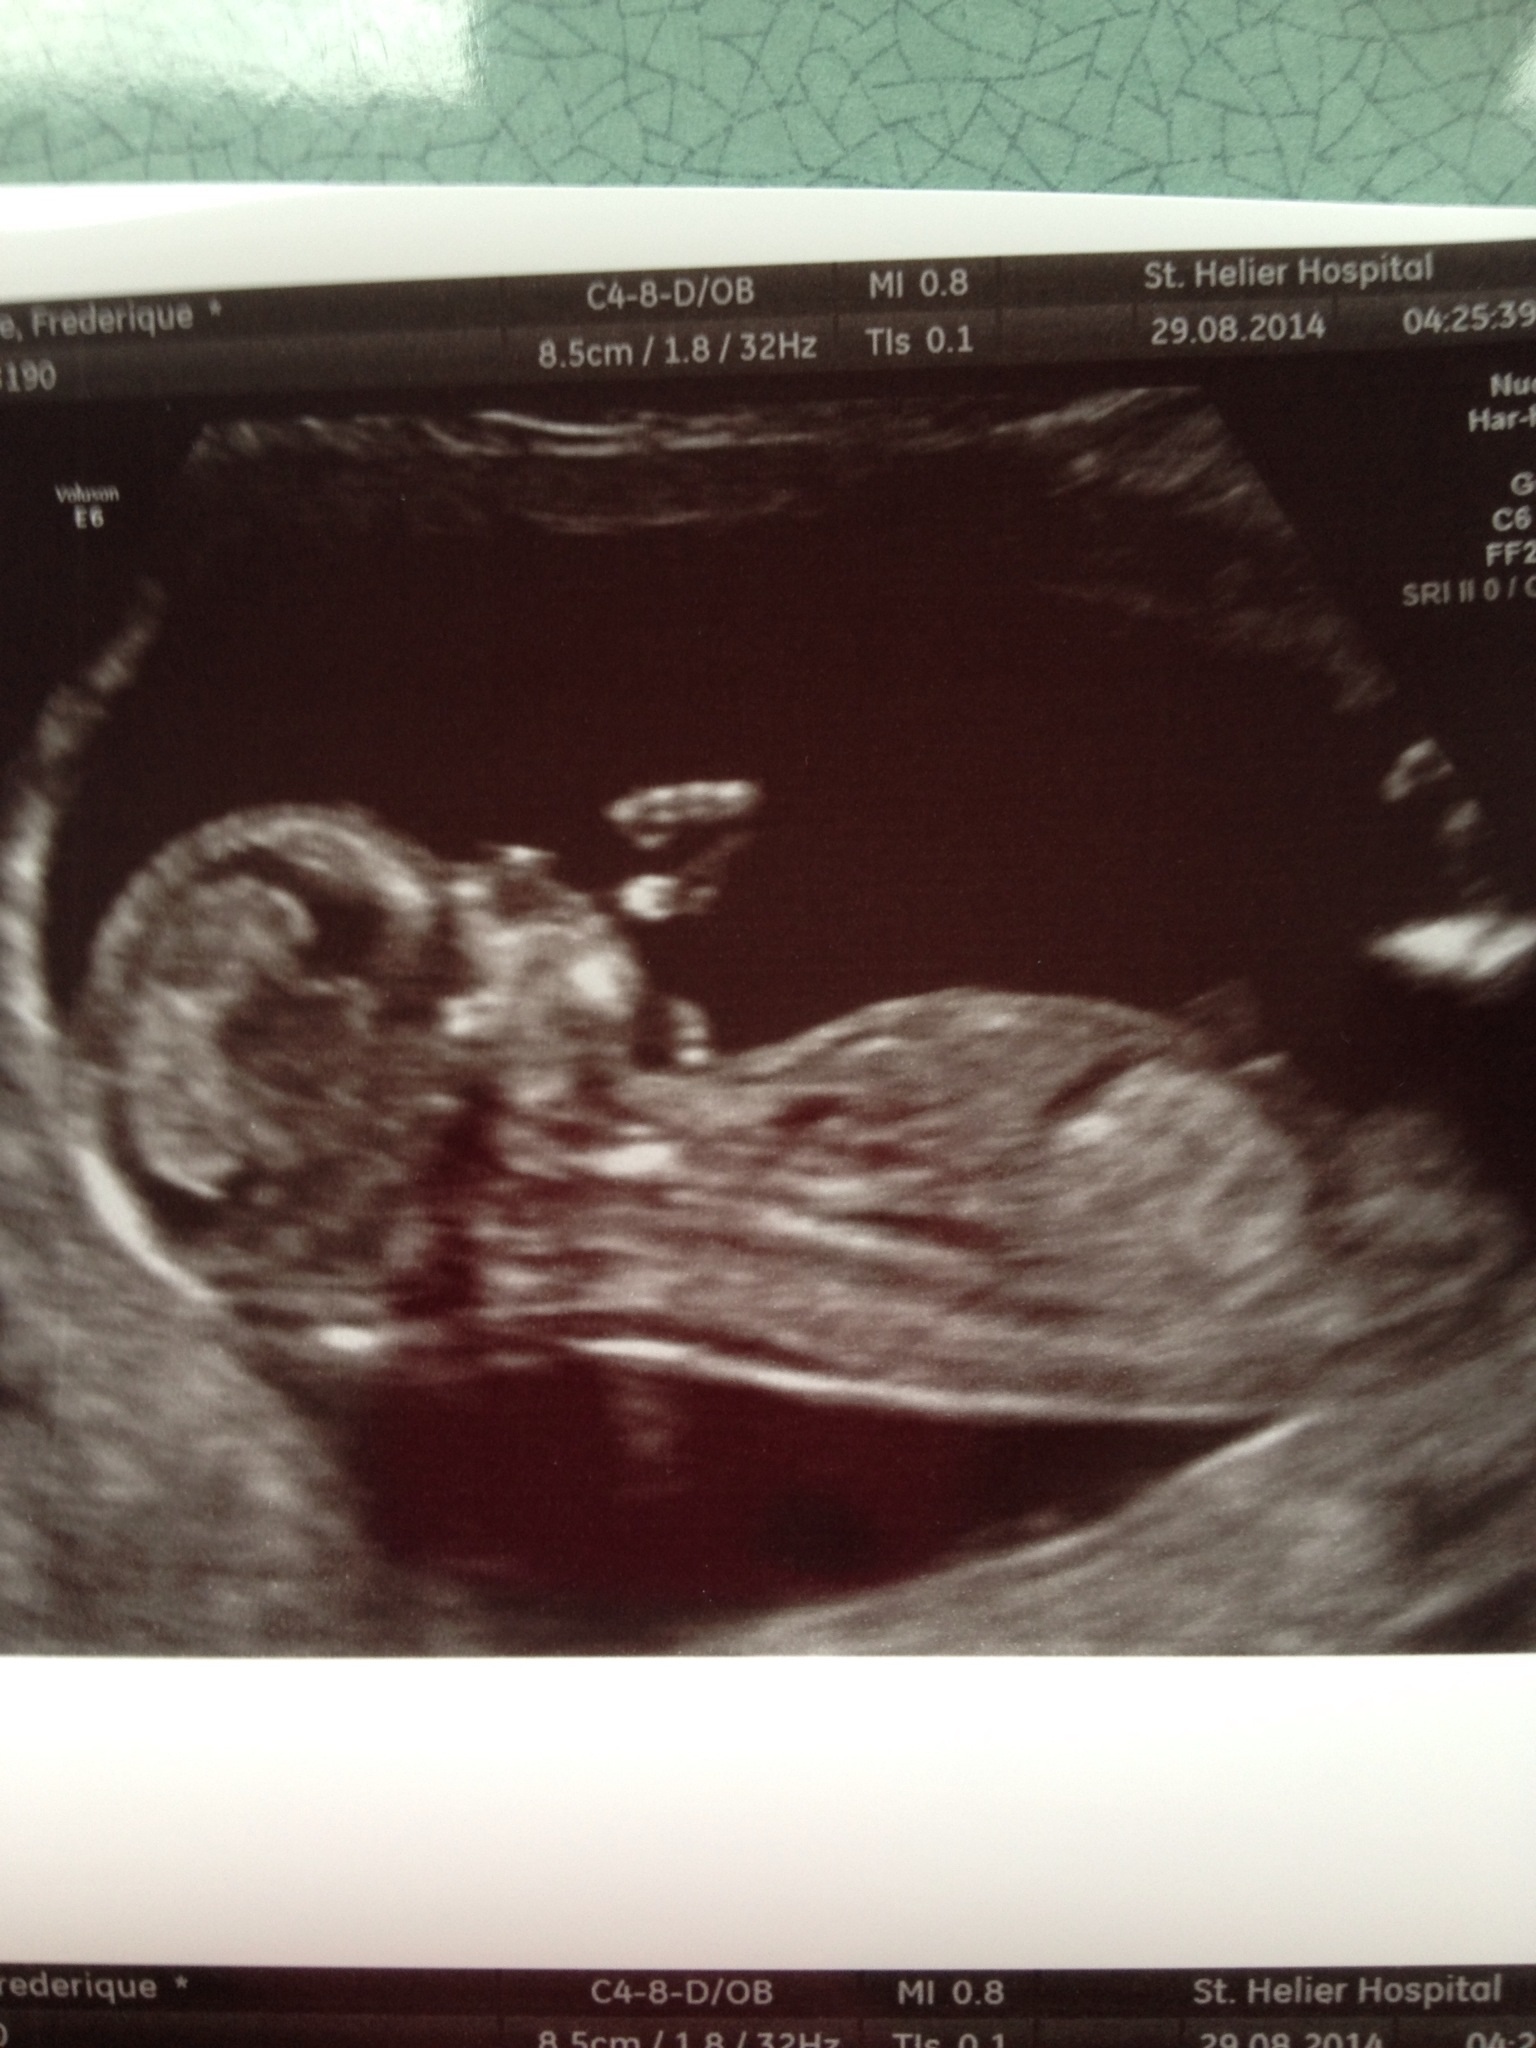

Hi There! These are my 13weeks 5 days scan pics

Not sure if any show a nub - let me know what you think![]()

No nub, but lean boy based on skull. Update when you find out!

I"m going to guess girl because at that gestation I think we'd see more below the equator if it was a boy. But my confidence level is not real high, pics are not as clear as I like.

Your tech did a fab job at NOT capturing the nub. Lol. I have no guess for you. I just had to laugh at three pics and I'm not seeing a thing!!